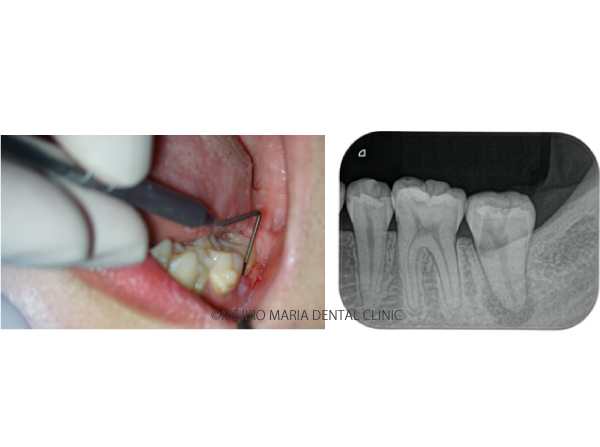

• 目白マリア歯科【症例】複雑な歯根形態(樋状根 (といじょうこん))に対する、精密根管治療のアプローチ(再根管治療)の治療前治療後のレントゲン画像

2020.11.28

【症例】複雑な歯根形態「樋状根」(といじょうこん)に対する、精密根管治療のアプローチ(再根管治療)